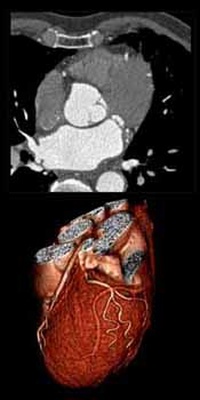

- Improved Detection of Atherosclerosis in Computed Tomography Images using Computational Fluid Dynamics by Habib C. Bou Sleiman

- Segmentation and tree extraction of coronary arteries in MSCT datasets by Victoria Quirante Ruiz

- Dual-Energy CT - Benefits for the Assessment of Atherosclerosis by Simon Eugster and Luca Regazzoni

- Classification of atherosclerosis in coronary arteries by Habib C. Bou Sleiman

- Boundary extraction of coronary arteries by Alessandro Rigazzi

- Automatic heart segmentation in CT datasets by Thomas Wismer